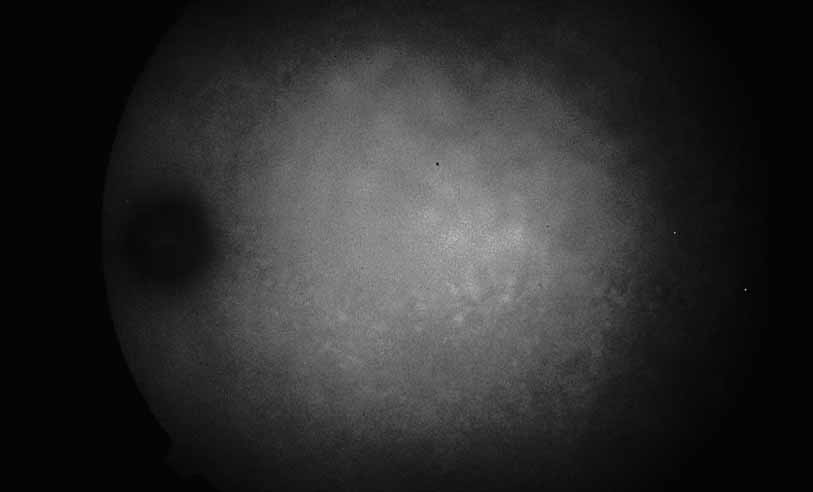

Fig. 28 Serpiginous choroiditis. ICG angiography early frame shows multiple hypofluorescent spots in the location of the lesions seen on color photography.

Fig. 29 Serpiginous choroiditis. ICG angiography later frame shows multiple hypofluorescent spots in the location of the lesions seen on color photography.